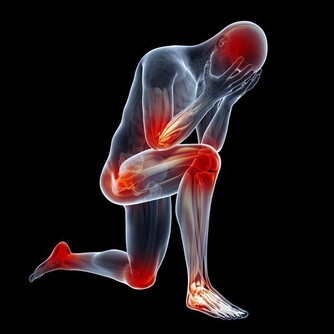

如果血管發生堵塞,或者血管異常窄,那麼氧氣的運輸以及物質循環就會被影響,甚至受到阻礙,那麼身體需要氧氣的各個器官組織也會出現異常,功能不能正常實現,身體的健康受到危害,嚴重的話會引發更多的心腦血管疾病,危及生命。

一、血管發生堵塞,腳會出現3個異常,若佔一個,提醒你要注意了

*****1、異常一:腳麻*****

血管堵塞,血液不流通,會導致腳經常發麻。

*****2、異常二:腳走路會不穩*****

血管堵塞,會發生走路不穩易摔倒的現象。

*****3、異常三:腳腫*****

血管堵塞,血液的流通受阻,進而就會造成腳經常水腫。